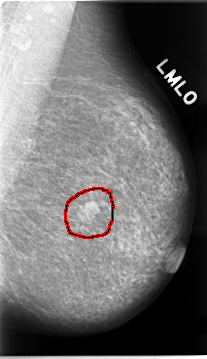

FILE: C_0023_1.LEFT_MLO.OVERLAY

TOTAL_ABNORMALITIES 1

ABNORMALITY 1

LESION_TYPE MASS SHAPE LOBULATED MARGINS MICROLOBULATED

ASSESSMENT 5

SUBTLETY 5

PATHOLOGY MALIGNANT

TOTAL_OUTLINES 1

BOUNDARY